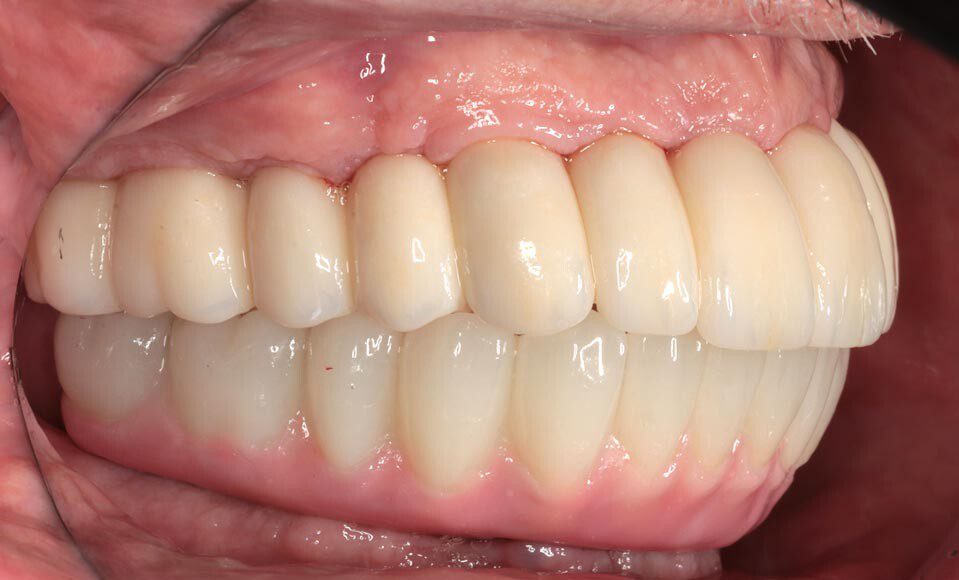

Prototype try-in, smile. The temporary bridges are removed and the prototypes placed. This is where the most scrutiny takes place as we want the patient and family to be thrilled with the appearance and bite. This is the last time changes can be made.